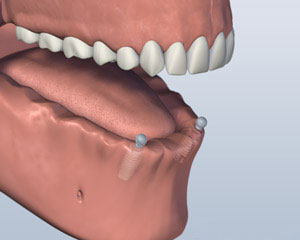

2. 植入放置

2. 植入放置

2. 植入放置

2. 植入放置